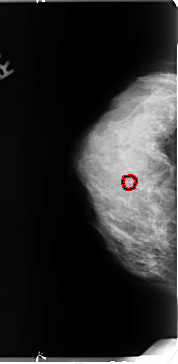

B_3127_1.LEFT_MLO

FILE: B_3127_1.RIGHT_MLO.OVERLAY

TOTAL_ABNORMALITIES 1

ABNORMALITY 1

LESION_TYPE CALCIFICATION TYPE PLEOMORPHIC DISTRIBUTION CLUSTERED

ASSESSMENT 4

SUBTLETY 3

PATHOLOGY BENIGN

TOTAL_OUTLINES 1

BOUNDARY